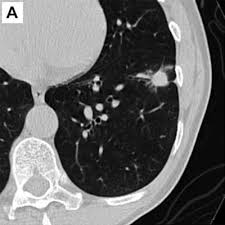

"폐결절(lung nodule)"은 폐 조직 내에서 직경 3cm 이하의 원형 또는 타원형 덩어리를 말합니다. 일반적으로 엑스레이나 CT 촬영에서 발견되며, 단독으로 존재하는 경우가 많지만 여러 개 나타날 수도 있습니다.

폐결절 진단은 주로 영상검사와 조직검사를 통해 이루어집니다.

- 영상 검사

- 흉부 X-ray: 초기 발견 용이, 해상도 낮음

- CT(컴퓨터단층촬영): 크기, 모양, 경계, 칼슘 침착 확인